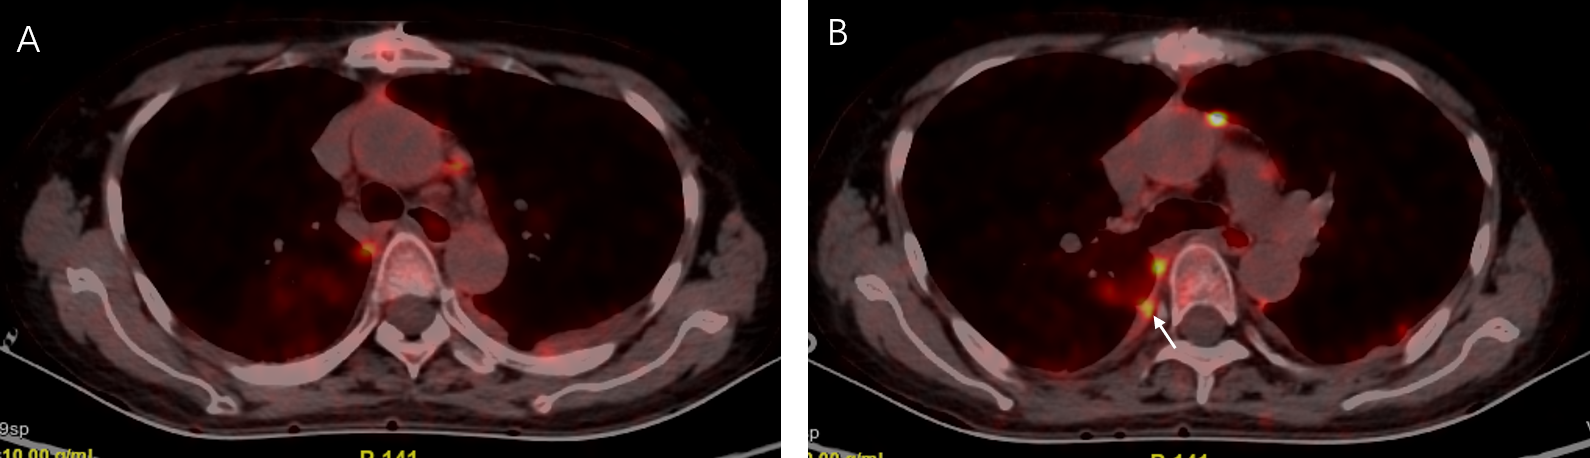

The patient was referred to our respiratory department for unexplained pleural effusion and dyspnea. In view of the patient’s history, we believed that both pleural metastases and pleuro-specific infection should be considered. PETCT was performed and showed multiple pleural thickening, and metabolic activity was found bilaterally with a maximum standard uptake value of 12.5 (Figure 2).

Figure 2

The positron emission tomography was performed 13 days later and showed multiple pleural thickening (A, B) and metabolic activity was found bilaterally with a maximum standard uptake value of 12.5 (B), arrow.